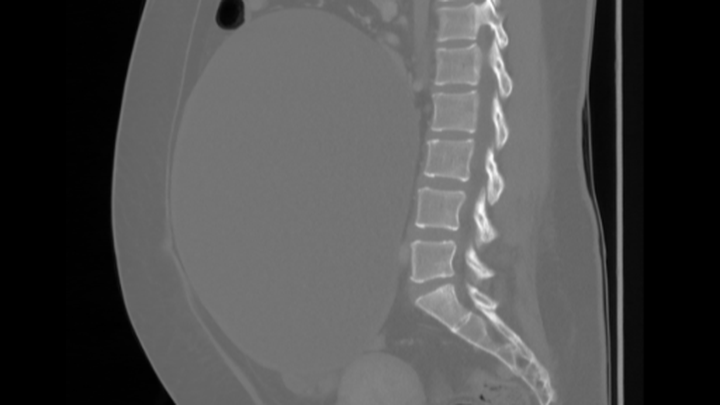

My name is Julieta. I’m currently in Canada and recently received heartbreaking medical news — I have a 25 cm cyst on my right ovary that could rupture at any moment. I also have another smaller cyst, about 3.8 cm on my left ovary.

A few days ago, I had to be admitted to the emergency room because of severe abdominal pain. I initially thought it was related to IBS (Irritable Bowel Syndrome), but after several tests and scans, the doctors discovered the true cause, the large ovarian cyst that’s now putting my health at serious risk.